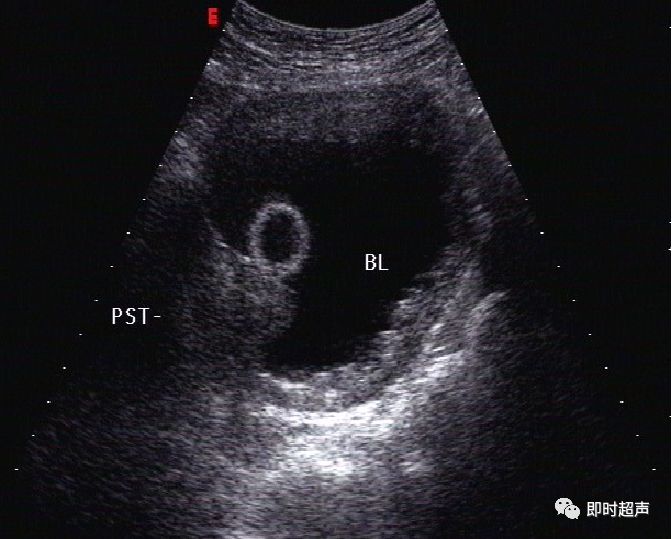

输尿管*尿喷**现象

(膀胱三角区、膀胱后壁两侧可见输尿管开口,排尿时可见输尿管口*尿喷**现象,尿流自后方斜向对侧前方,有断续光点移动。CDFI:显示尿流呈红色或橘红色。)